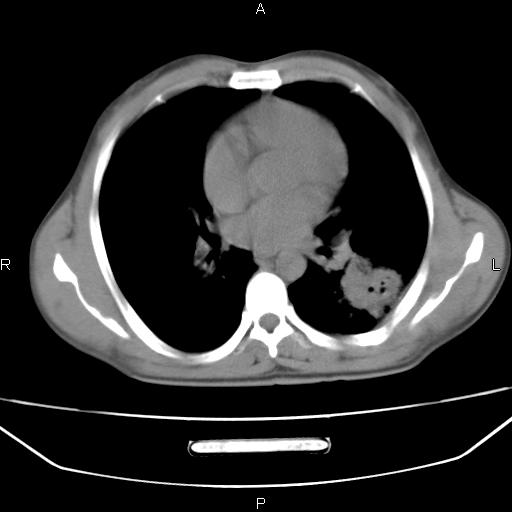

患者,男,40岁。间断发热,咳嗽二十余日。体温最高达38.9° 在当地诊所抗炎治疗三天后体温降至正常,患者自行停药。今又发热。胸片示,左下肺阴影。

左下肺片状高密度影,境界模糊,密度不均,考虑感染性病变可能性大,建议抗炎治疗后复查。左肺门增大,不除外占位性病变,必要时支气管镜检。